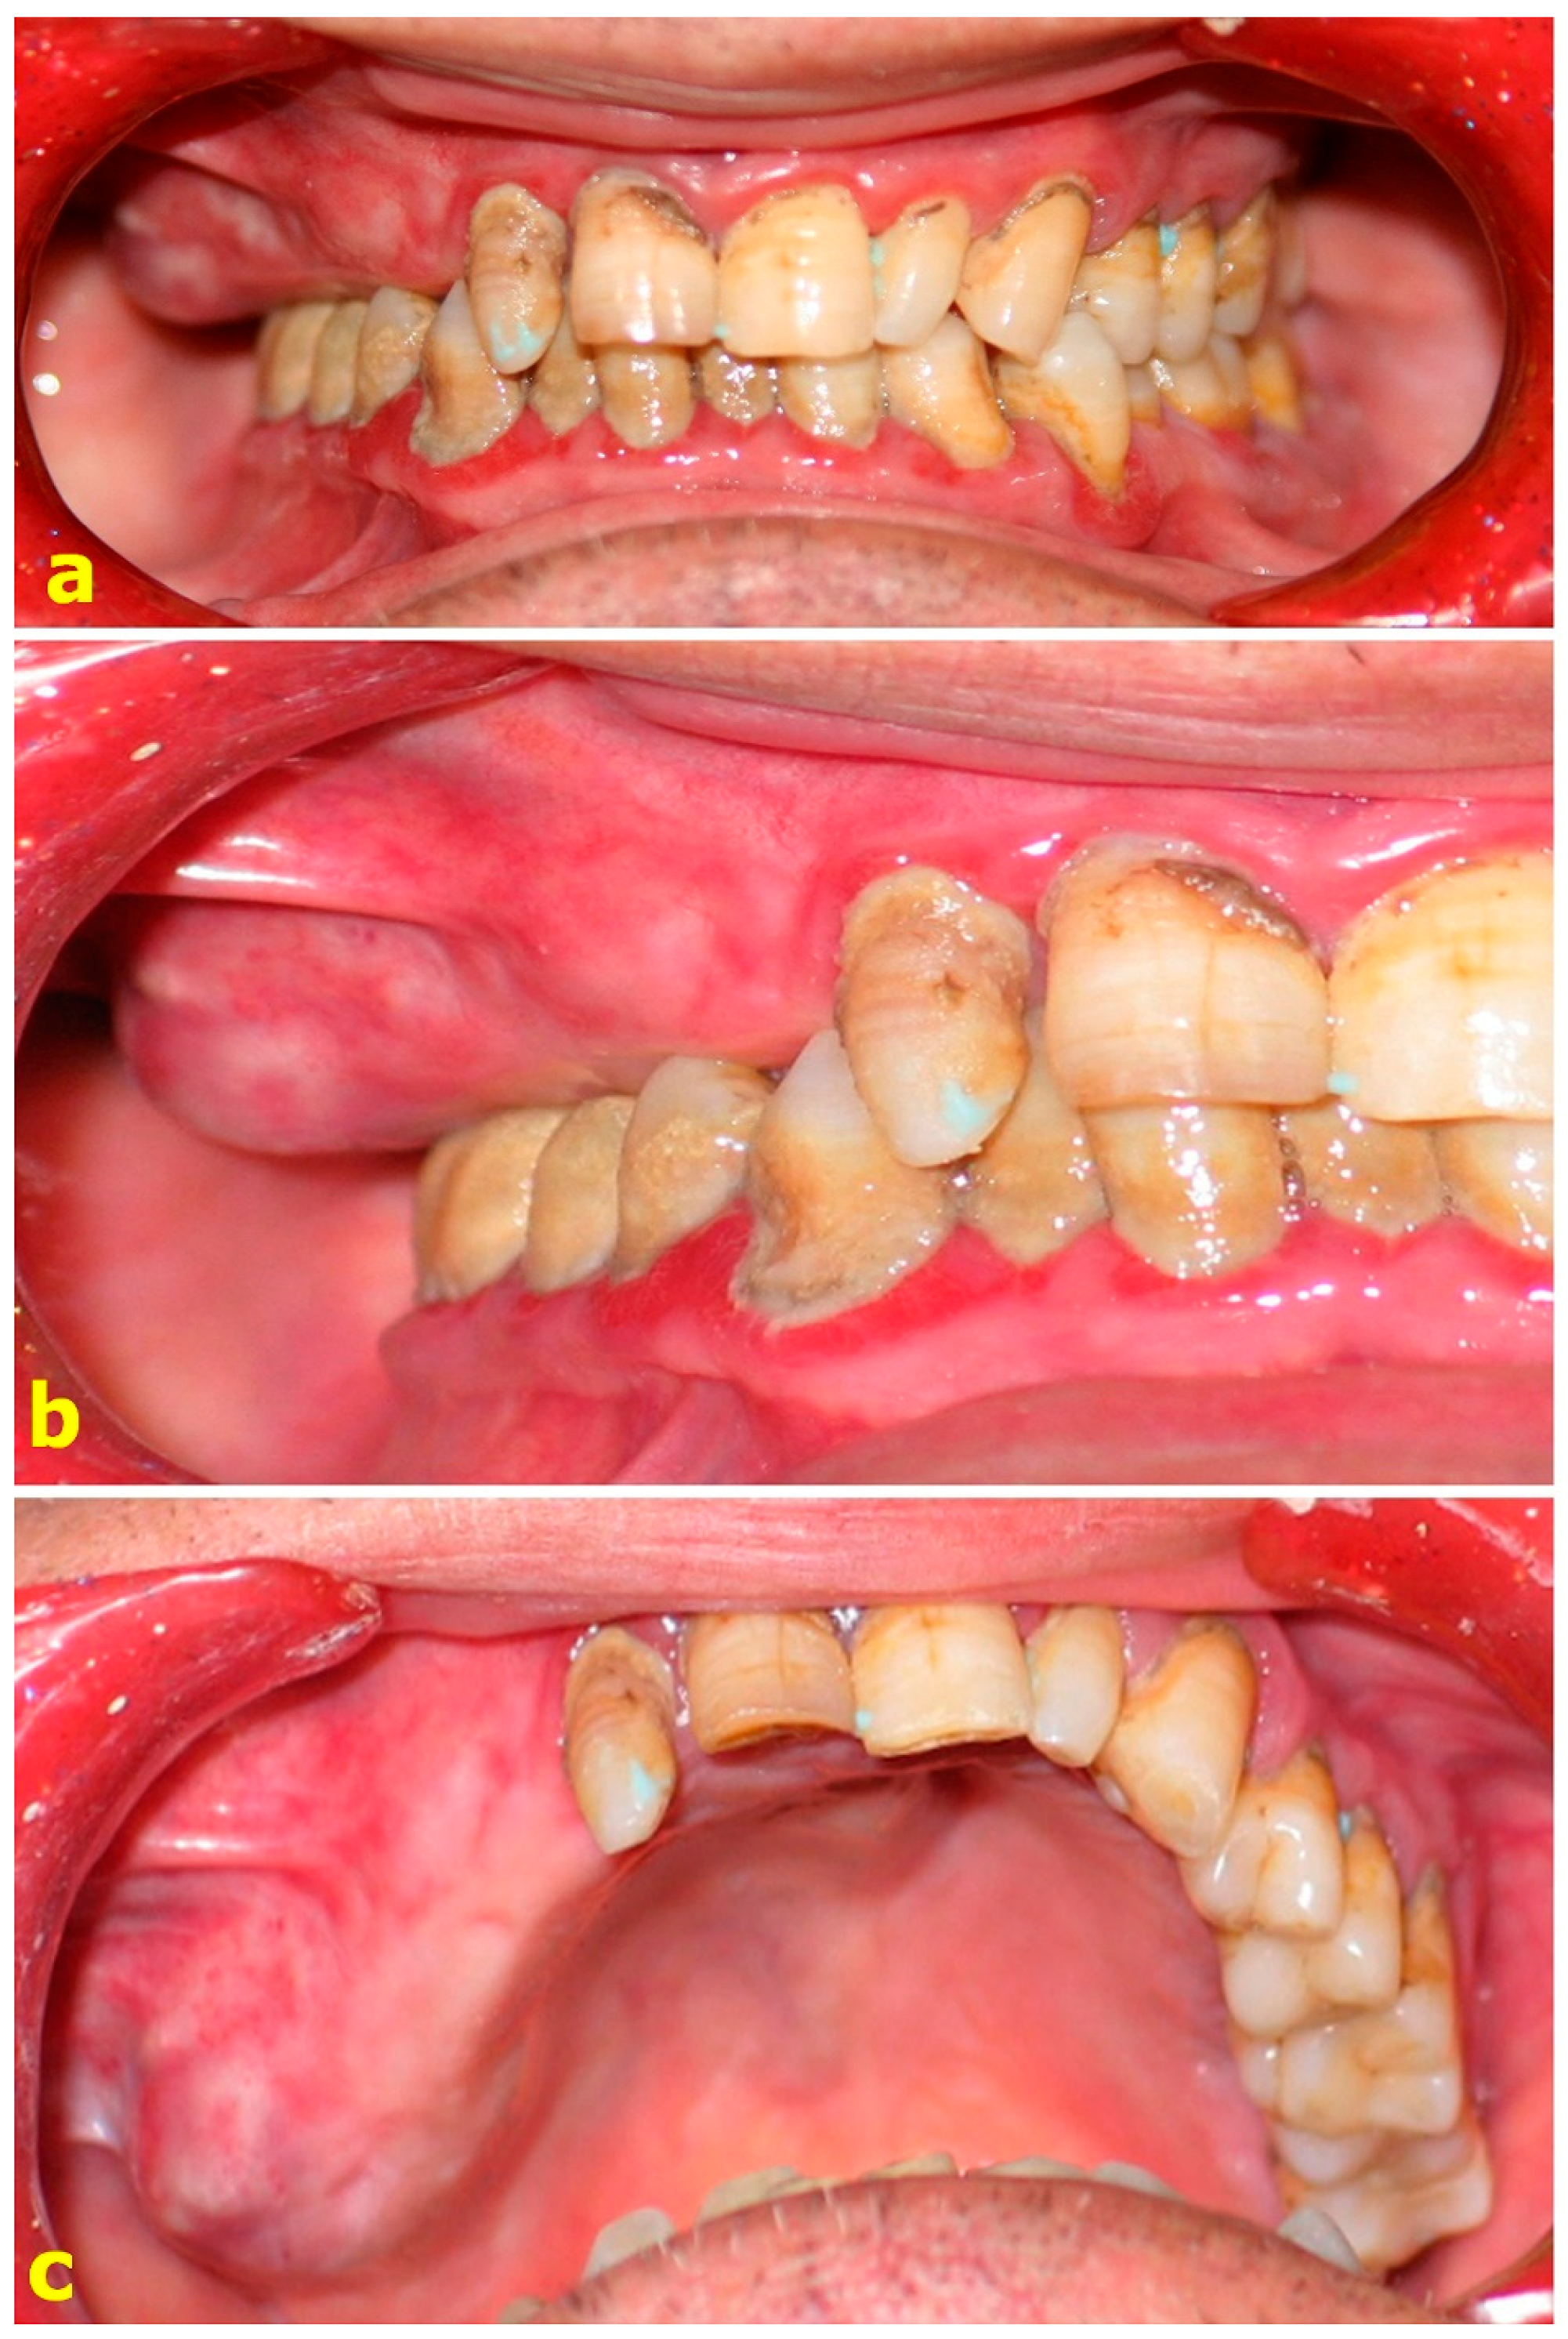

In this study, forty-one patients aged between 20 and 73 years with surgically acquired partial maxillary defects were included. Ten of these patients were edentulous, twenty were partially edentulous, and eleven were dentulous before the surgery (Figure 1, Figure 2 and Figure 3). The consents of the patients and the ethical committee were obtained.

Figure 1. Clinical aspect of a lesion. (a,b) Pre-operative intraoral view of the lesion. (c) The lesion is in the edentate region to the right of the maxilla.